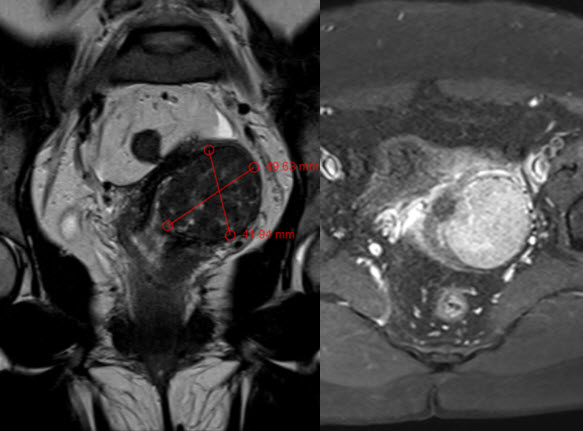

Hình ảnh chụp MRI khối u xơ tử cung lớn

Hình ảnh chụp MRI: khối u xơ tử cung lớn KT: 41x42x50 mm ở đoạn eo tử cung đè ép vào thân tử cung.